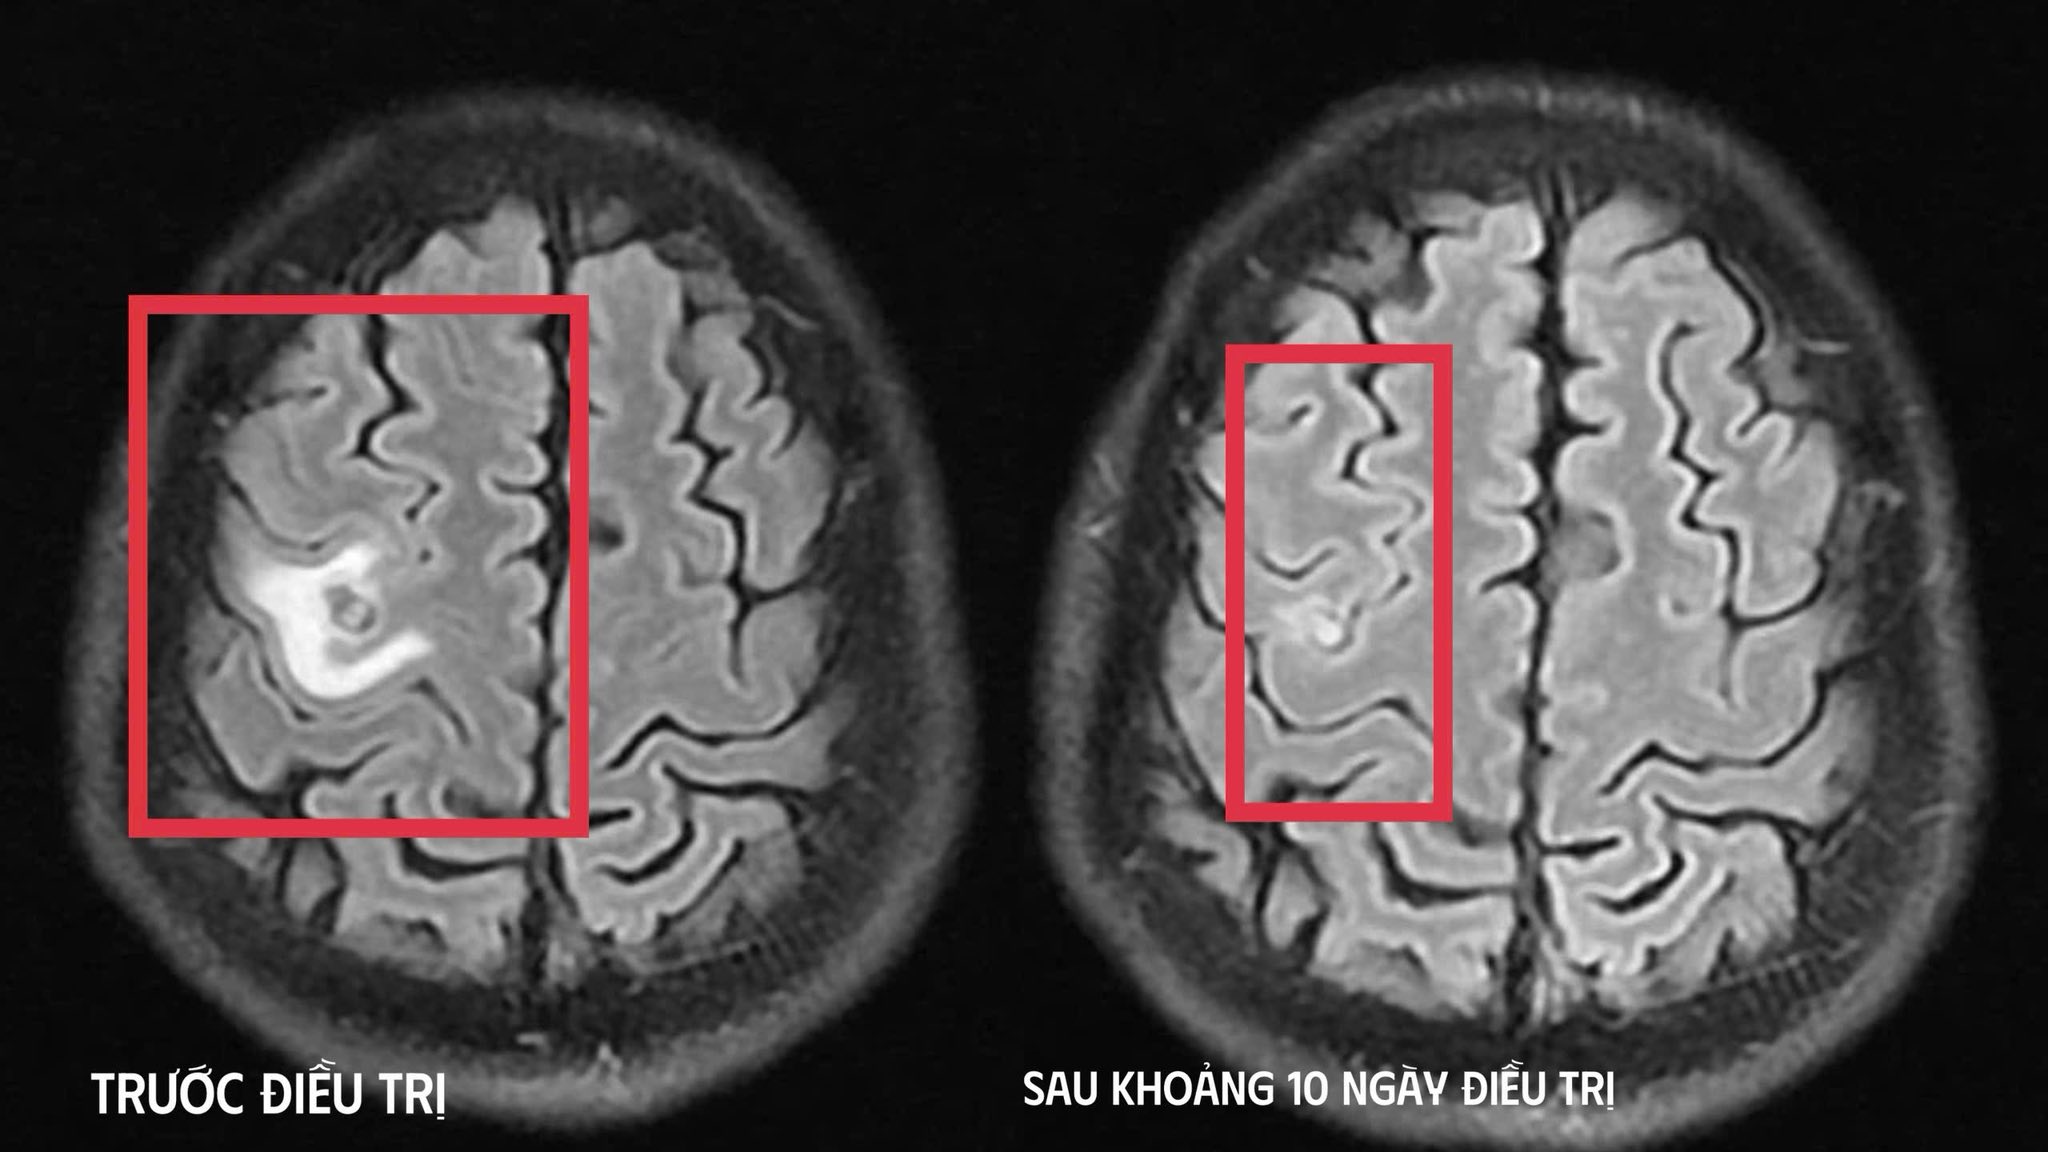

Bệnh nhân được chụp cộng hưởng từ (MRI) sọ não, phát hiện tổn thương dạng nang nhỏ tại thùy trán trái, kích thước khoảng 11 x 7 mm, xung quanh có phù não nhẹ. Hình ảnh này hướng nhiều đến tổn thương do ký sinh trùng hơn là u não nguyên phát. Các xét nghiệm huyết thanh học về vấn đề gì? tiếp tục được chỉ định, trong đó xét nghiệm kháng thể kháng sán dây chó cho kết quả dương tính, giúp khẳng định chẩn đoán tổn thương não do ký sinh trùng.

Sau khi xác định nguyên nhân, bệnh nhân được điều trị nội khoa theo phác đồ, kết hợp kiểm soát triệu chứng và theo dõi sát diễn biến thần kinh. Sau khoảng 10 ngày điều trị nội trú, tình trạng bệnh nhân cải thiện rõ rệt, hết tê tay, không còn xuất hiện cơn co giật, không đau đầu hay chóng mặt, toàn trạng ổn định. Người bệnh được cho ra viện và tiếp tục điều trị ngoại trú đủ liệu trình kéo dài 4 tuần.

Khi tái khám gần một tháng sau, kết quả chụp cộng hưởng từ cho thấy tổn thương não thu nhỏ ( cụ thể hình dạng nang) rõ rệt, phù não giảm, không còn dấu hiệu tiến triển, đáp ứng điều trị tốt. Bệnh nhân tiếp tục được chỉ định thêm một đợt thuốc củng cố và theo dõi lâu dài.